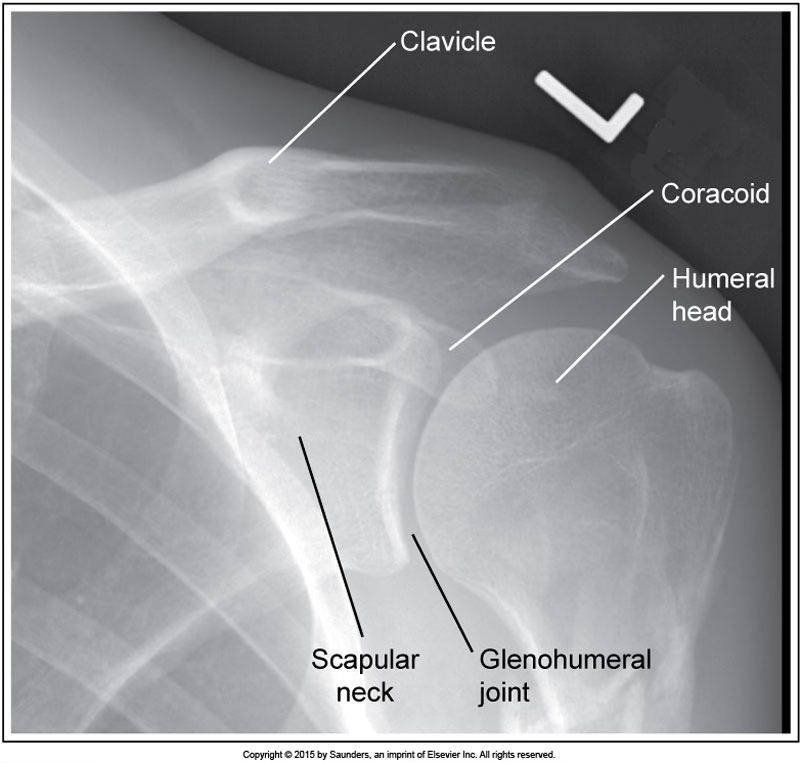

grashey

accurate positioning